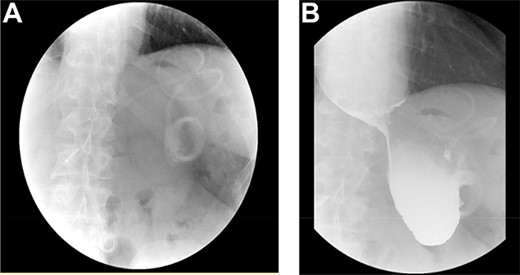

As part of the assessment, computed tomography (CT) coronary angiogram study was performed and it demonstrated a large fluid-filled oesophagus causing partial compression of the left atrium. Barium swallow (Fig. 1A and B), CT chest and abdomen (Fig. 2A and B) and transthoracic echocardiography (TTE) showed a 7.1-cm dilated oesophagus causing left atrial compression and a small hiatal hernia (Fig. 3).

(A) LAGB more inferior and rotated consistent with band slippage; (B) marked distension of the oesophagus and contrast hold up at the level of the slipped band.